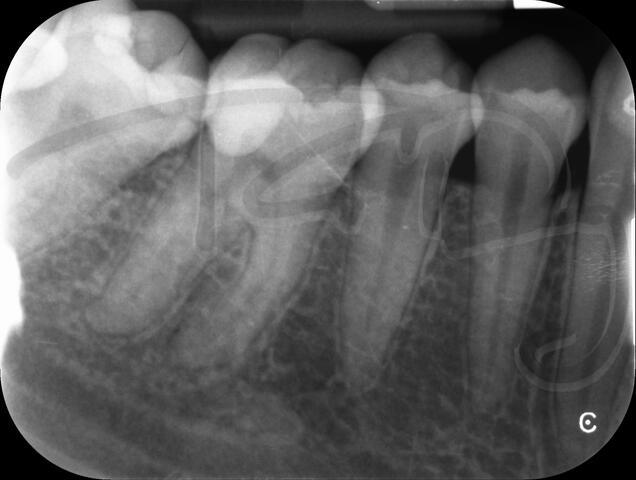

I am pleased to take endodontic referrals. Curved canals >30 degrees and potentially greater than 50 degrees can be negotiated. Sclerosed canals accessed. Post spaces prepared and the patient returned to you ready to restore.In most cases existing crowns, bridges and veneers can be retained with the endodontic access aesthetically restored after the full canal network has been treated.In the first instance I would prefer a radiograph and a brief list of patient expectations and a tooth history.

I really enjoy undertaking root canal treatments - rising to the challenge and helping people out of dental pain for the long term.I was privileged to be asked to speak at the 2016 BDA Conference, where I have a lecture about providing quality endodontic outcomes to patients, working as a generalist. Avoiding problems and pitfalls and maximising efficiency. One of the main matters that he covered was understanding that what is seen on plane radiography is utterly misleading and should not be the criteria by which a generalist continues treatment once it has been started.

At the 2016 BDA Conference, Thomas spoke about providing quality endodontic outcomes to patients, working as a generalist. Avoiding problems and pitfalls and maximising efficiency. One of the main matters that he covered was understanding that what is seen on plane radiography is utterly misleading and should not be the criteria by which a generalist continues treatment once it has been

started.